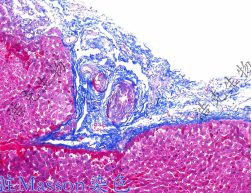

Masson染色

masson染色即麗春紅酸性品紅-苯胺藍染色,是用于檢測動物組織中膠原纖維最常見的染色方法之一。能夠?qū)⒛z原纖維染成藍色,肌纖維、細胞質(zhì),紅細胞等染成紅色??捎糜阼b別膠原纖維和肌纖維,并顯示各種組織膠原纖維含量及纖維化程度。

masson染色機制:masson染色由麗春紅2R,酸性品紅,苯胺藍等幾種陰離子染料進行混合染色。根據(jù)染料的分子量大小及組織的滲透性不同,進而將不同的成份著染上不同的顏色,從而將其區(qū)分開來。組織的滲透性取決于組織的致密程度。膠原纖維結(jié)構(gòu)疏松多孔,與其他組織成份相比具有最大的滲透性。小分子量的染料易穿透結(jié)構(gòu)致密,滲透性低的組織,而大分子量的染料則只能進入結(jié)構(gòu)疏松,滲透性高的組織。麗春紅2R分子量480.43,酸性品紅分子量585.55,苯胺藍分子量737.74。所以在masson染色過程中滲透性高的膠原纖維會被大分子量的苯胺藍染上藍色,而肌纖維,細胞質(zhì)等其他成份會被小分子量的麗春紅和酸性品紅染成紅色。

骨組織的主要成分是膠原纖維。在骨生長及再生過程中,新生骨膠原纖維比較疏松,滲透性高會被大分子量的苯胺藍染上藍色。而隨著骨組織的生長,膠原纖維會逐漸變得更加致密,交聯(lián)更加緊密并沉積大量的鈣離子,排列更加規(guī)則逐漸形成成熟的編織骨,滲透性逐漸降低,故在masson染色中被小分子量的麗春紅和酸性品紅染成紅色。進而將新生的早期骨組織和成熟的骨組織區(qū)分開來。

染色結(jié)果:膠原纖維、粘液、軟骨呈藍色;肌纖維、纖維素和紅細胞呈紅色。